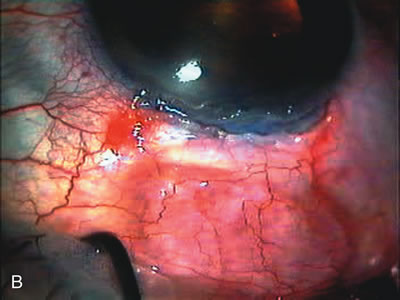

Fig. 8. Bleb appearance after limbus-based versus fornix-based conjunctival flaps. Even though the IOP is thought to be equivalent between limbus and fornix-based conjunctival flaps, the final bleb appearance varies considerably. A. During a limbus-based approach, an incision through conjunctiva 10 mm posterior to limbus will sever through multiple arterial vessels, increasing the likelihood of an avascular bleb. B. The tissues are dissected down to the sclera further cutting feeder vessels from Tenon's capsule. C. The wound is closed inciting a cascade of wound healing events that may ultimately lead to scarring producing a barrier to aqueous flow. D. This leads to walling off of a bleb that has lost some of its overlying vascularity (pale cystic avascular bleb). E. During a fornix-based conjunctival approach, the incision is made at the limbus and tissues undermined. F. The incision is closed at the limbus; no conjunctival vessels are severed over the bleb area. G. This fosters the formation of a shallow diffuse pale bleb with a normal vessel pattern.

During preoperative slit-lamp biomicroscopy, the surgeon evaluates the condition of the conjunctiva and decides on a fornix-based or a limbus-based conjunctival approach.174–177 There are definite advantages and disadvantages of each approach (Table 3). With proper wound construction, there appears to be very little difference in long-term IOP control between the two incisional groups. However, the long-term bleb appearance varies considerably between the two incisional groups,178 with a limbus-based conjunctival flap more likely to develop a cystic bleb especially if an antimetabolite is used179 (Fig. 8).